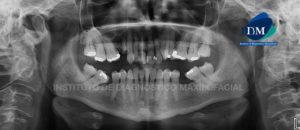

Paciente masculino de 27 años de edad acude al Instituto de Diagnóstico Maxilofacial por evaluación de terceras molares. Motivo por el cual se le realiza